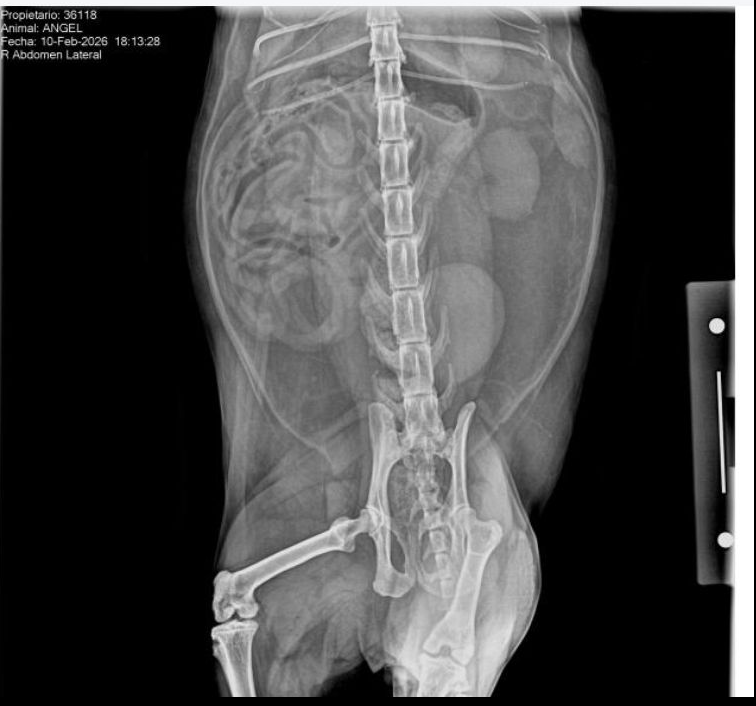

During visiting hours the vet updated us and explained that the X-rays revealed one of his kidneys appears shrunken, meaning the other kidney had been working in overdrive to compensate and has finally crashed.